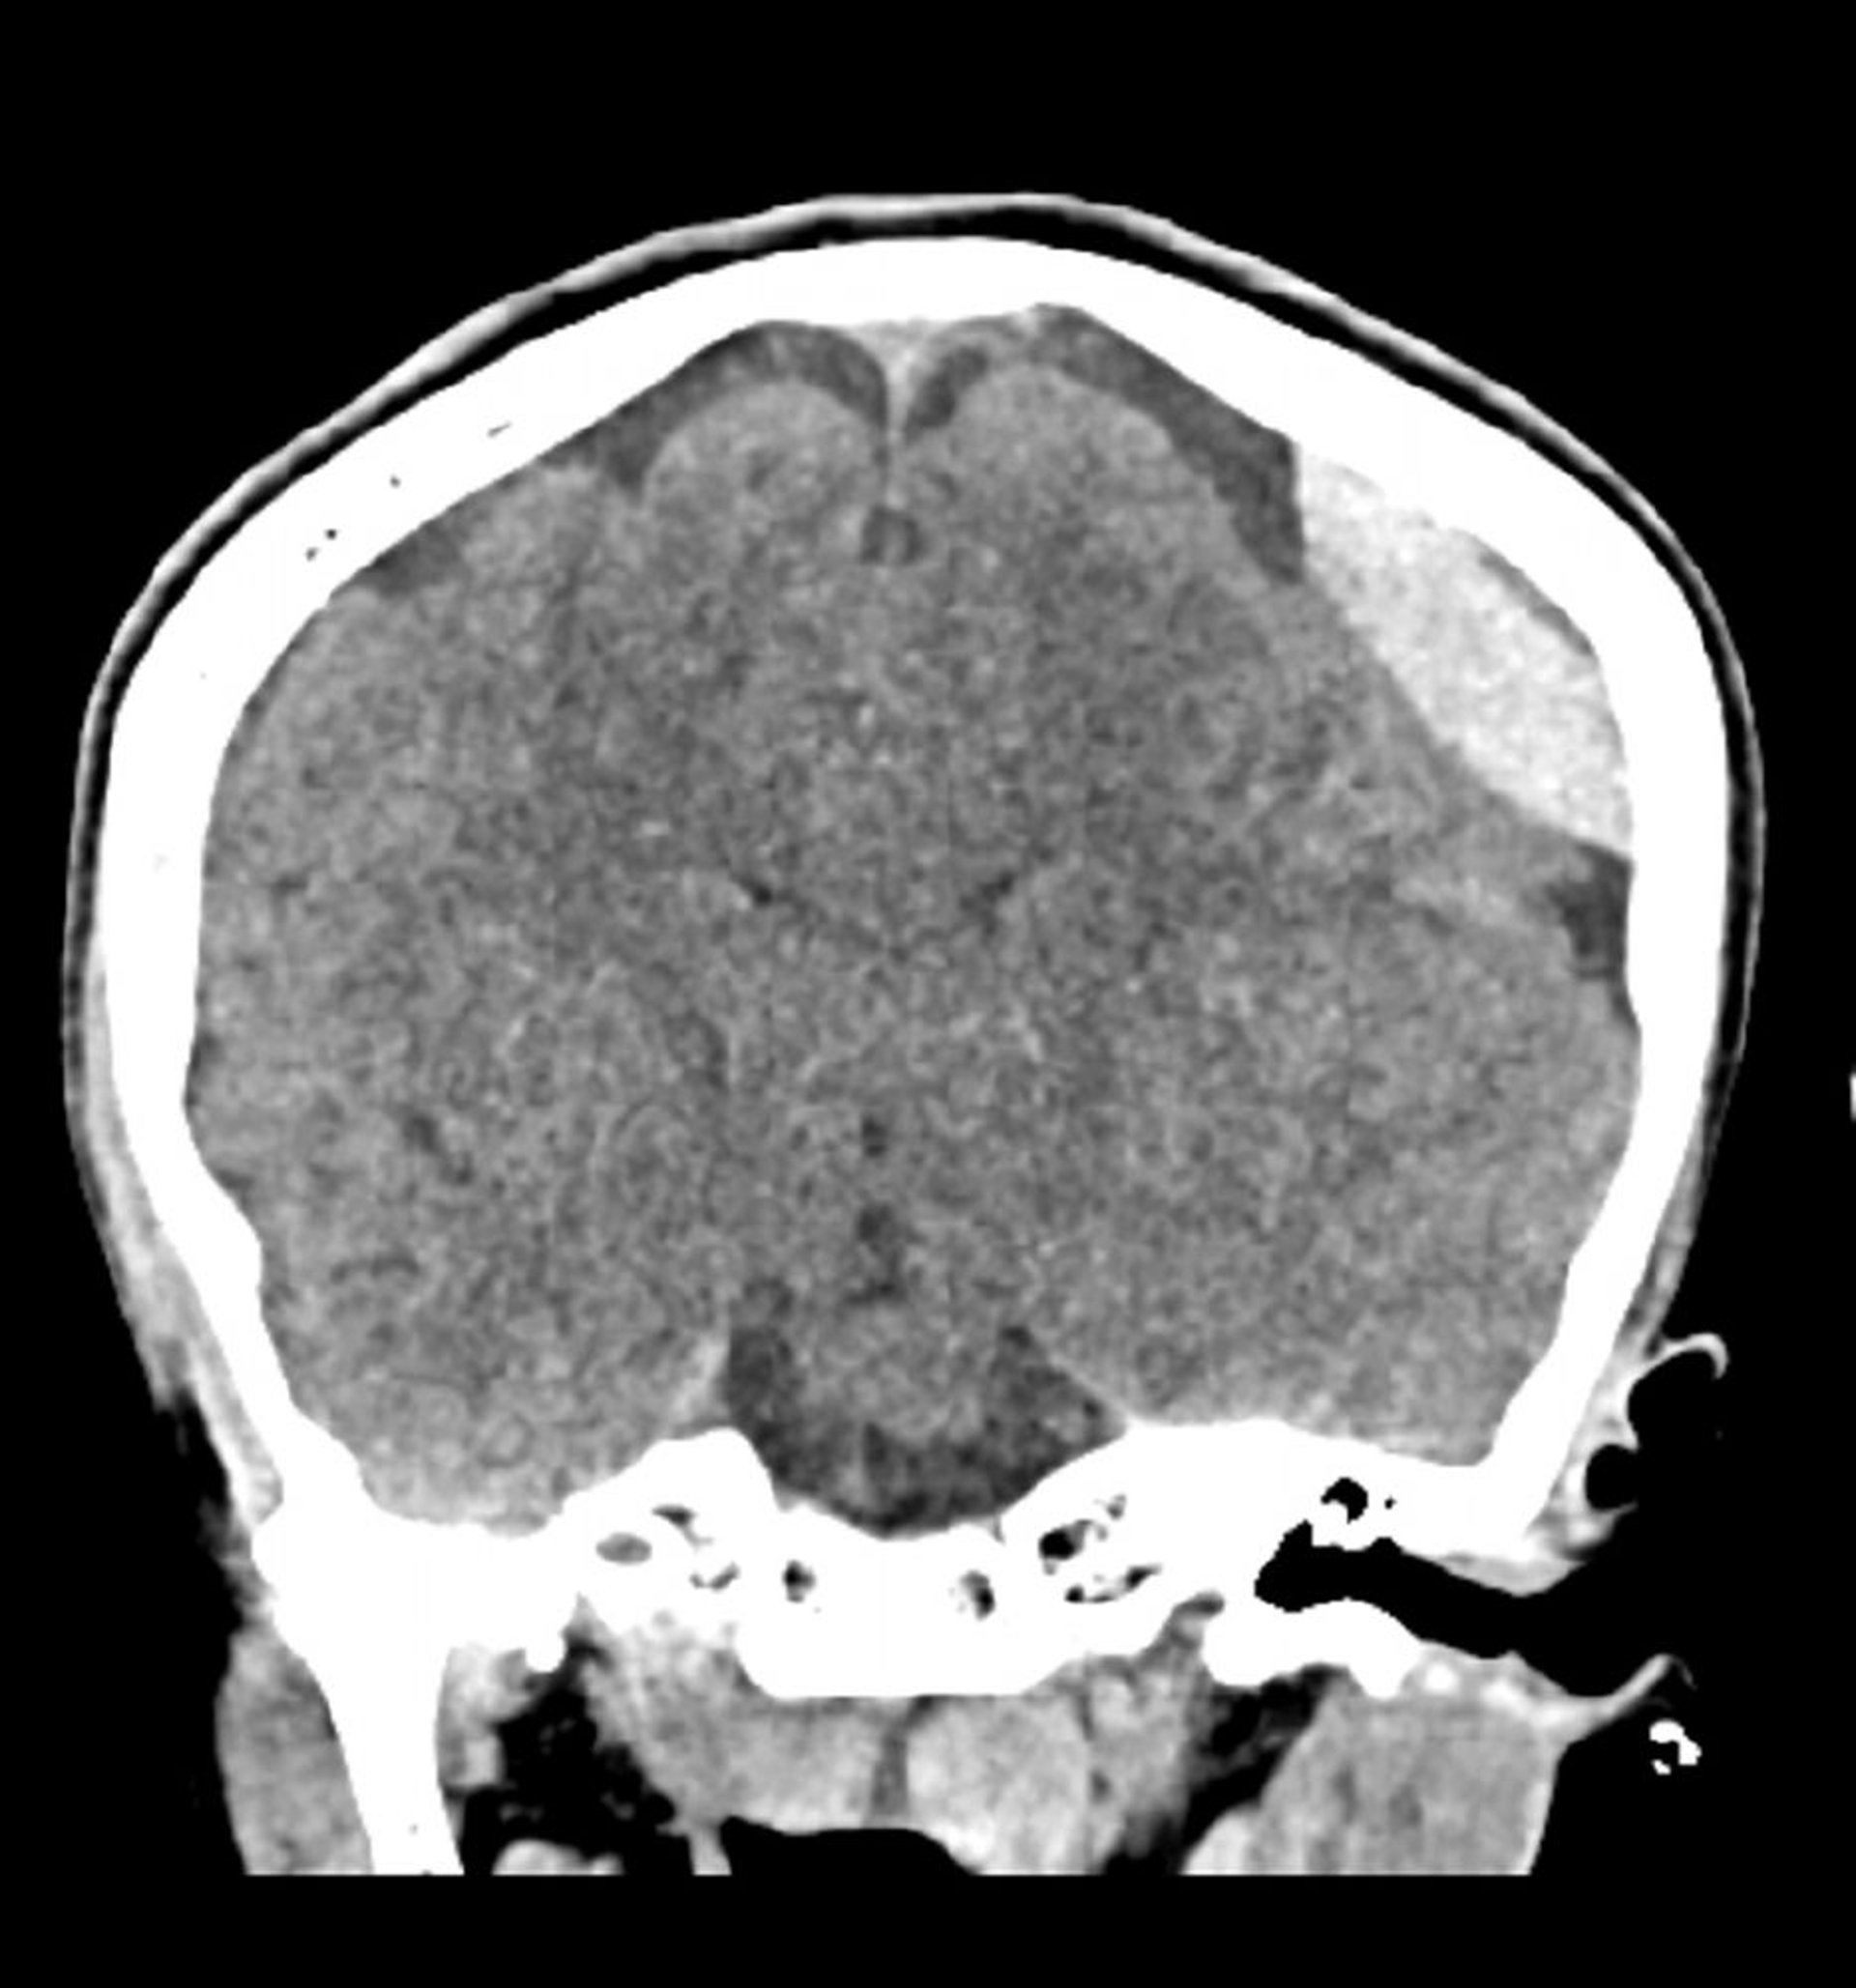

Hemorragia epidural (TC coronal)

Hiperdensidad lentiforme clásica (lente o cristalino) que no se extiende a través de las líneas de sutura.